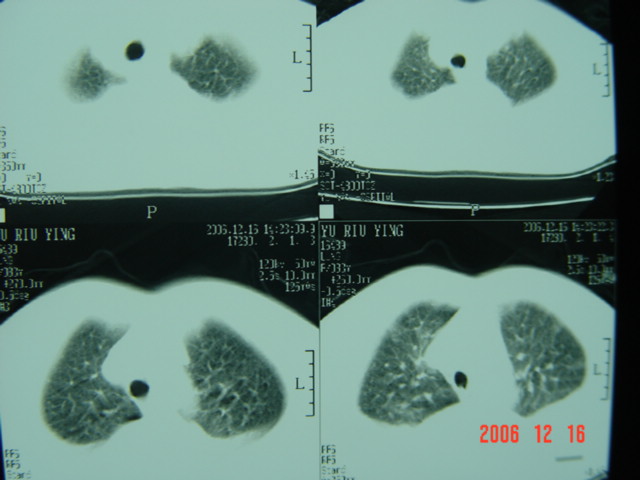

标题: CT5663:女、83岁,轻微咳嗽、左下胸痛。 [打印本页]

标题: CT5663:女、83岁,轻微咳嗽、左下胸痛。

左第八肋腋侧呈膨胀性骨质破坏,内侧见软组织密度肿块。左肺舌段呈楔形实变,基底近胸壁,尖端向肺门。双侧胸壁后缘见新月形水样密度区。

考虑:1、左第8肋骨转移瘤;

2、左肺舌叶肺栓塞可能性大;

3、双侧中量胸腔积液。

考虑1左侧肋骨破坏考虑转移瘤。2左下肺部分肺不张或实变,左肺舌段片团影考虑肺癌可能性大[肺梗塞--往往有明显的胸痛,呼吸急促或困难等表现]。3双侧肺淤血及双侧胸腔积液考虑心功能不全所致可能性大